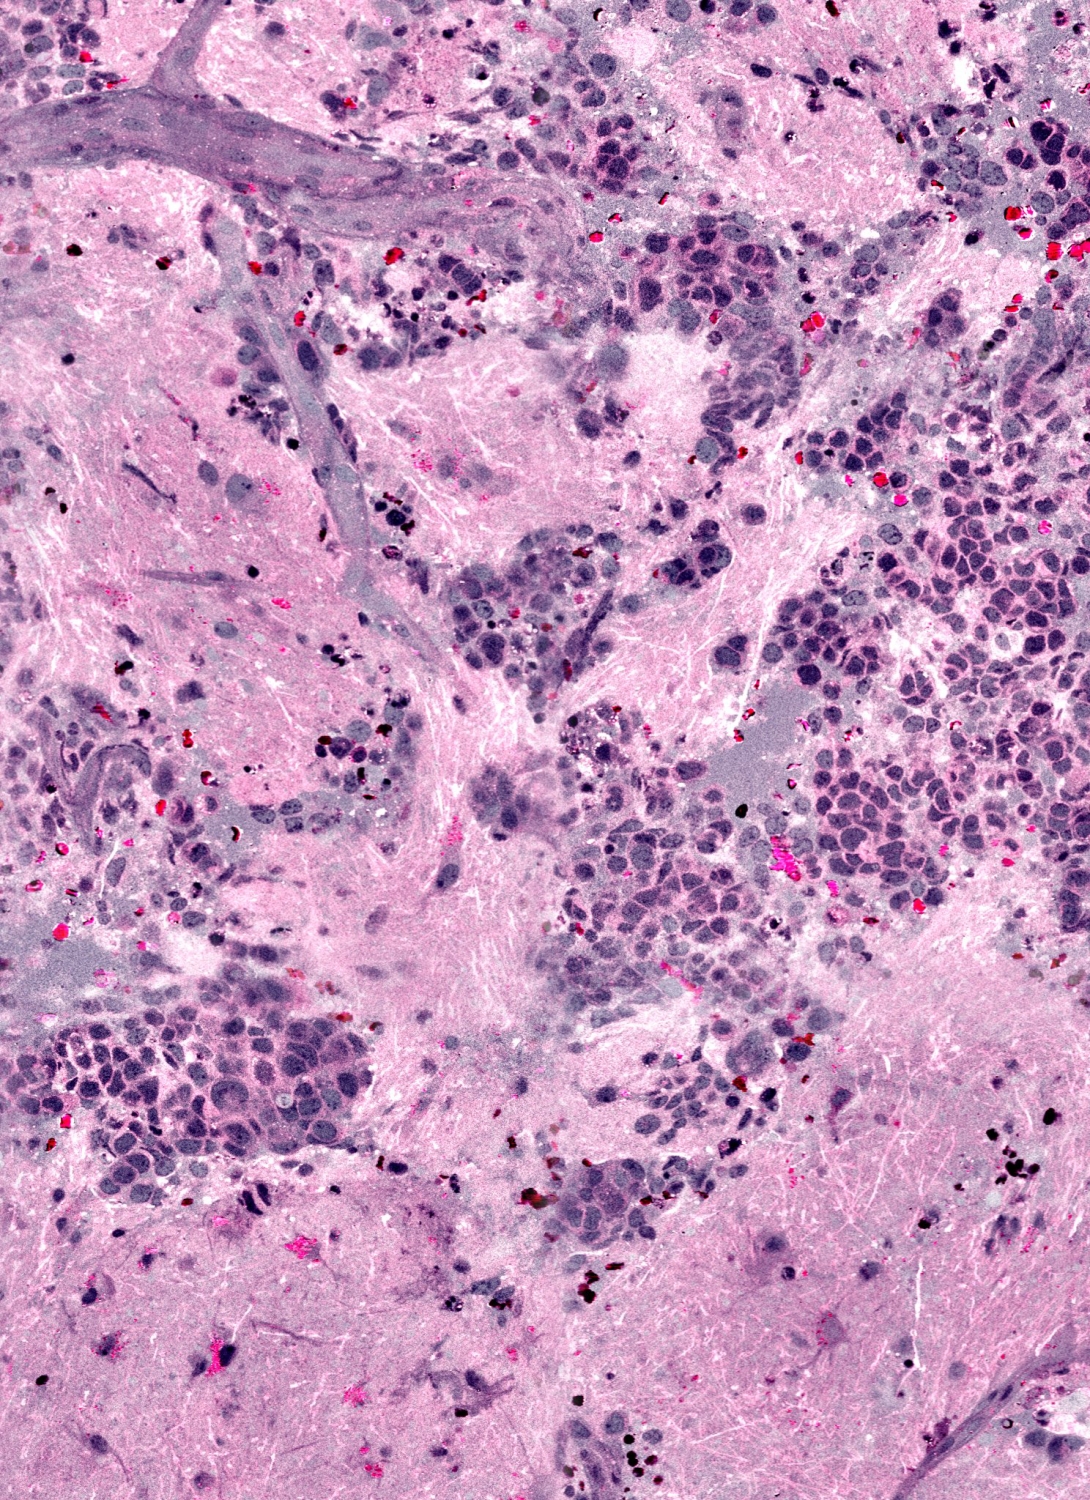

To interpret the samples, researchers developed SRH, which creates images similar to those currently in use.

SRH uses virtual coloring to highlight the cellular and architectural features of brain tumors, with a result resembling traditional staining. The pathologist is then able to differentiate the tumor tissue from normal brain as usual.

"It's very similar to what we currently do in our intraoperative diagnosis, with the exception that the tissue is fresh, has not been processed or stained," says senior author Sandra Camelo-Piragua, M.D., assistant professor of pathology at U-M.